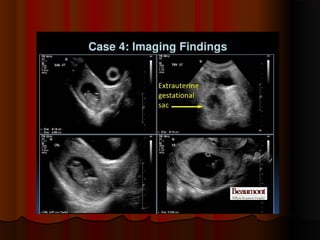

????????

placental abruptionplacental abruption..

Crescent ofCrescent of avascularavascular

low echogenicitylow echogenicity

between placenta andbetween placenta and

uterine wall consistentuterine wall consistent

withwith placentalplacental

abruptionabruption..

placental abruptionplacental abruption.. Crescent ofCrescent ofavascularavascular low echogenicitylow echogenicity between placenta andbetween placenta and uterine wall consistentuterine wall consistent withwith placentalplacental abruptionabruption..